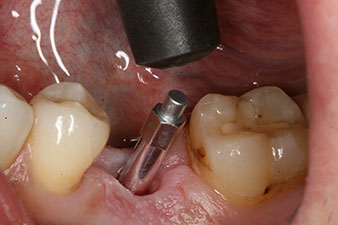

The torque used for the machine-driven placement was 43 Ncm. In addition, after screwing a measuring post (SmartPeg) specially matched to the implant, the ISQ value was measured with the probe of the W&H Osstell ISQ module.

This module is an optional extra for the W&H Implantmed and is docked to the implantology motor (see Fig. 11). The dimensionless ISQ value immediately after insertion was 64 orovestibular and 68 mesiodistal (maximum value = 100).

The implant stability is better described as micromobility and is best measured by resonance-frequency analysis (RFA) (7, 8). Measurements are best made in two directions, as in the case study (9). The technology is optionally available as a module that can be docked to the Implantmed implantology motor. A separate device is not required. The lower value is always applicable for the therapy. Measured values are displayed on the touch screen of the implantology motor as the implant-stability quotient (ISQ). Along with the torque curve for insertion and data on preparation of the implant bed, they can be recorded on a USB stick and used for documentation for the patient and the implant. Overall, it is a very user-friendly and reliable technology for everyday work in implantology, particularly in combination with the W&H Implantmed.